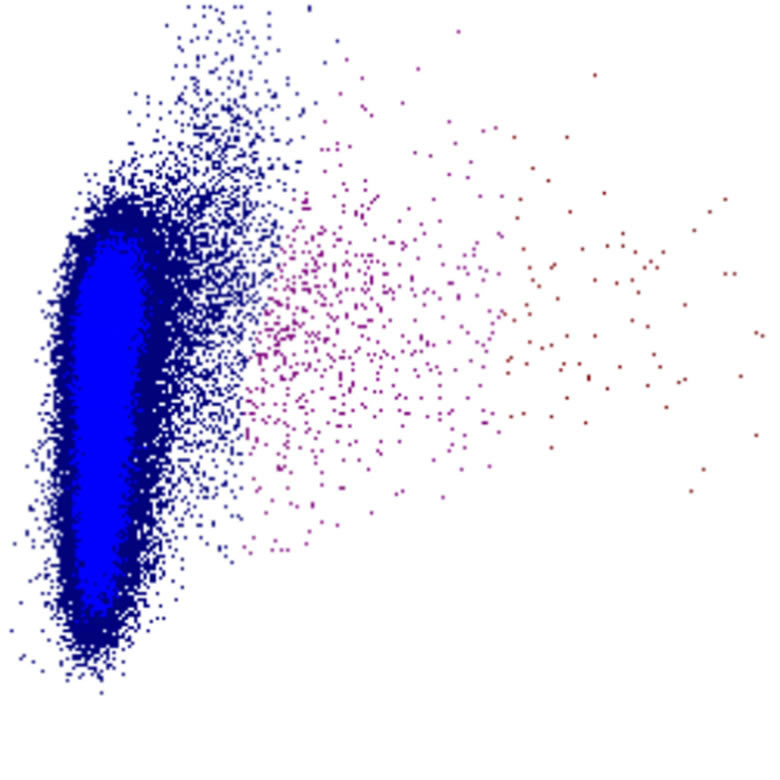

SFL scatter

SFL faible

SFL élevé